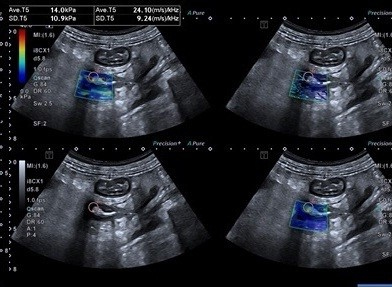

Group III patients are those with increased SWE and SWD and need corroborative tests to reach final diagnosis as these findings can be observed in early Crohn's disease, partially treated infective ileo-colitis (Figure 4). The ancillary imaging findings like increased bowel vascularity, regional lymph nodes, and mesenteric creeping fat sign may also be helpful imaging features in making a differential diagnosis. The ability to directly detect inflammation by the use of SWD has made SWE a unique tool to directly detect and quantify tissue inflammation, unlike the use of inflammatory serum biomarkers like C reactive protein, erythrocyte sedimentation rate, Interleukin levels which are all indirect markers. Even fecal calprotectin being a specific test of inflammatory bowel disease does not depict the site of bowel inflammation. Hence SWE becomes a tool with immense potential in the evaluation of all such patients.

Figure 4. A patient with Crohn disease with increased bowel stiffness of 14 kPa and SWD of 24.10 m/s/kHz.